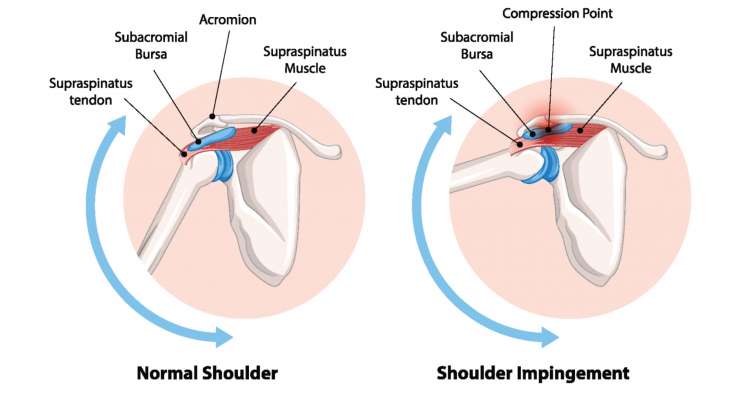

Субакромиальное ущемление

Субакромиальный импинджмент, то есть болезненный синдром ущемления под акромионом, профессор Франк Мартетшлегер сначала лечит консервативно, а при стойких симптомах — артроскопически, путем целенаправленной декомпрессии для разгрузки сухожилий.